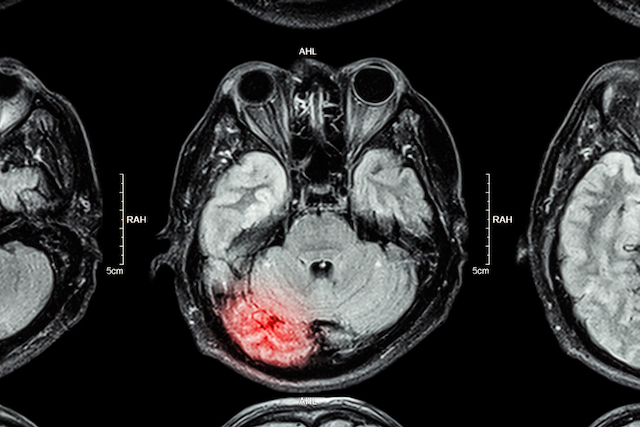

Serious injuries, or catastrophic injuries, are those that permanently or significantly impact your daily life. Amputation, brain injuries, and spinal injuries are three common examples.

They can occur in various circumstances, from road traffic accidents to workplace accidents and accidents in public spaces. Medical negligence is another leading cause of serious injuries in the UK, particularly regarding brain injuries and spinal injuries from badly performed or even unnecessary surgery.